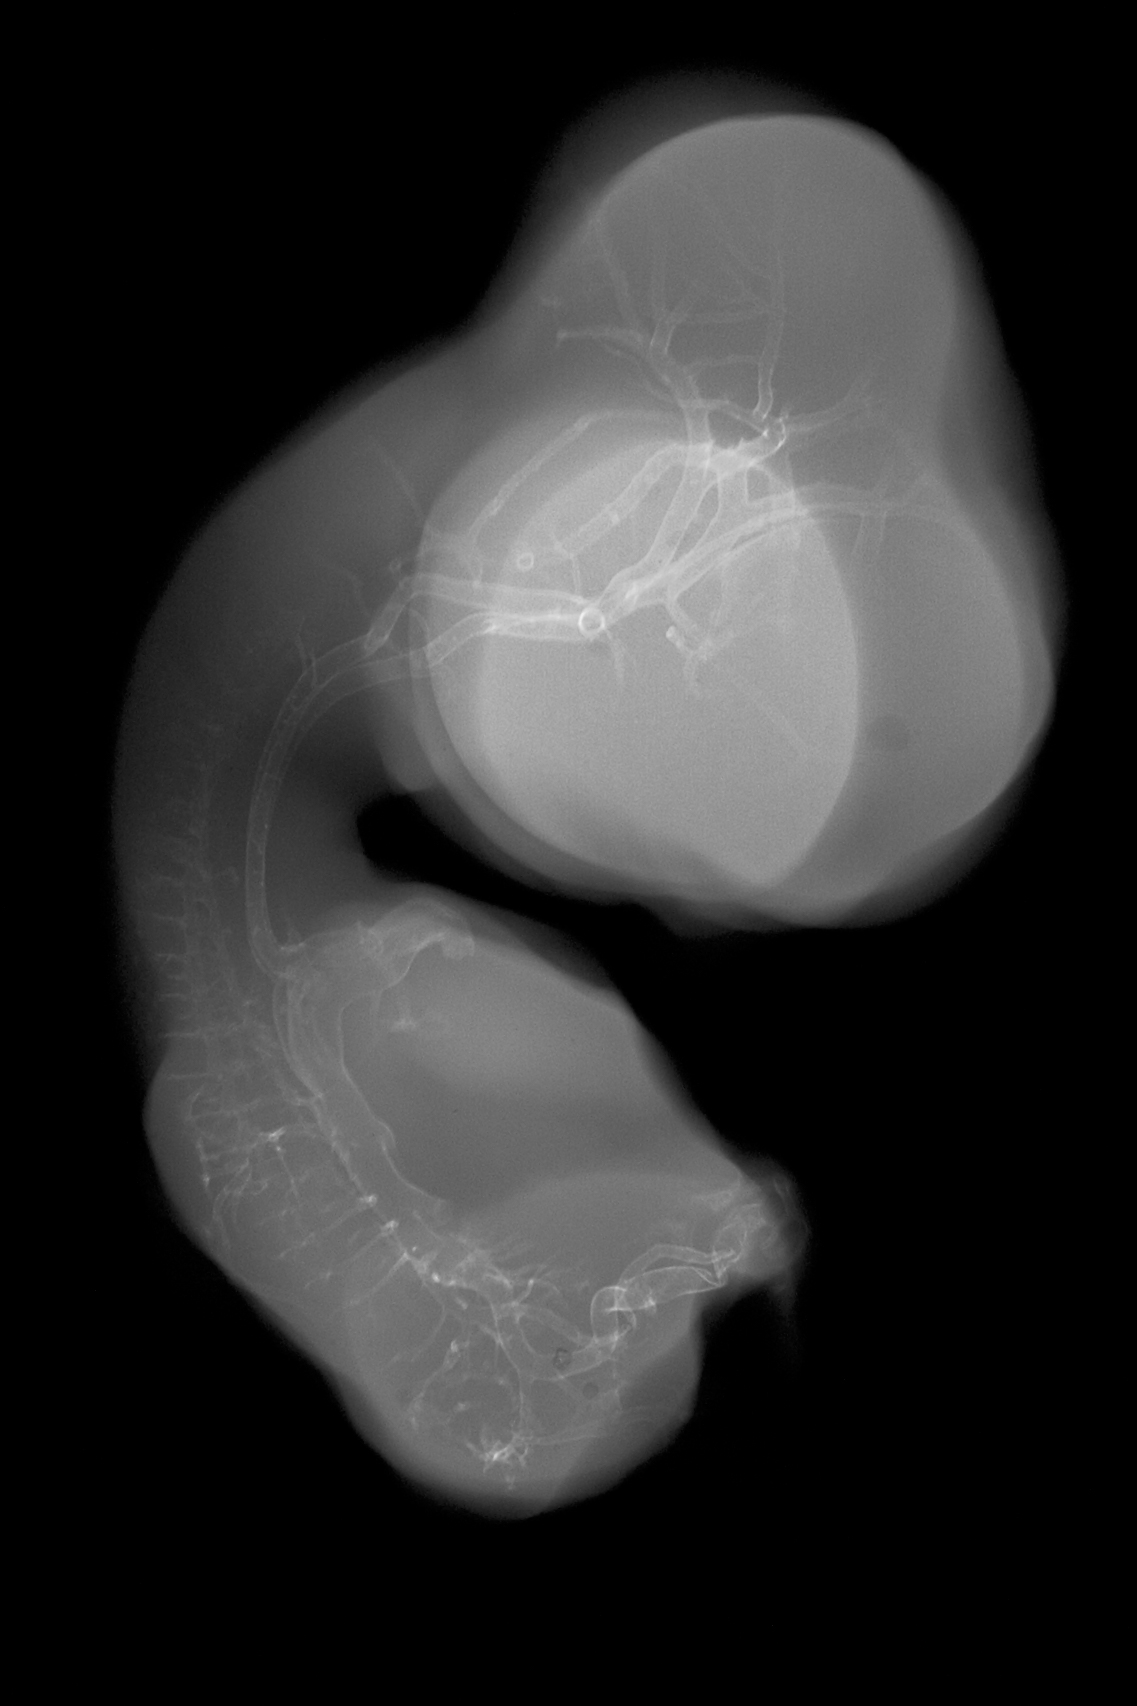

Chick Embryo Microangiography

Hamburger-Hamilton (HH) Stage 30 (approx. 6.5 days)

Stereo X-Ray Micrographs